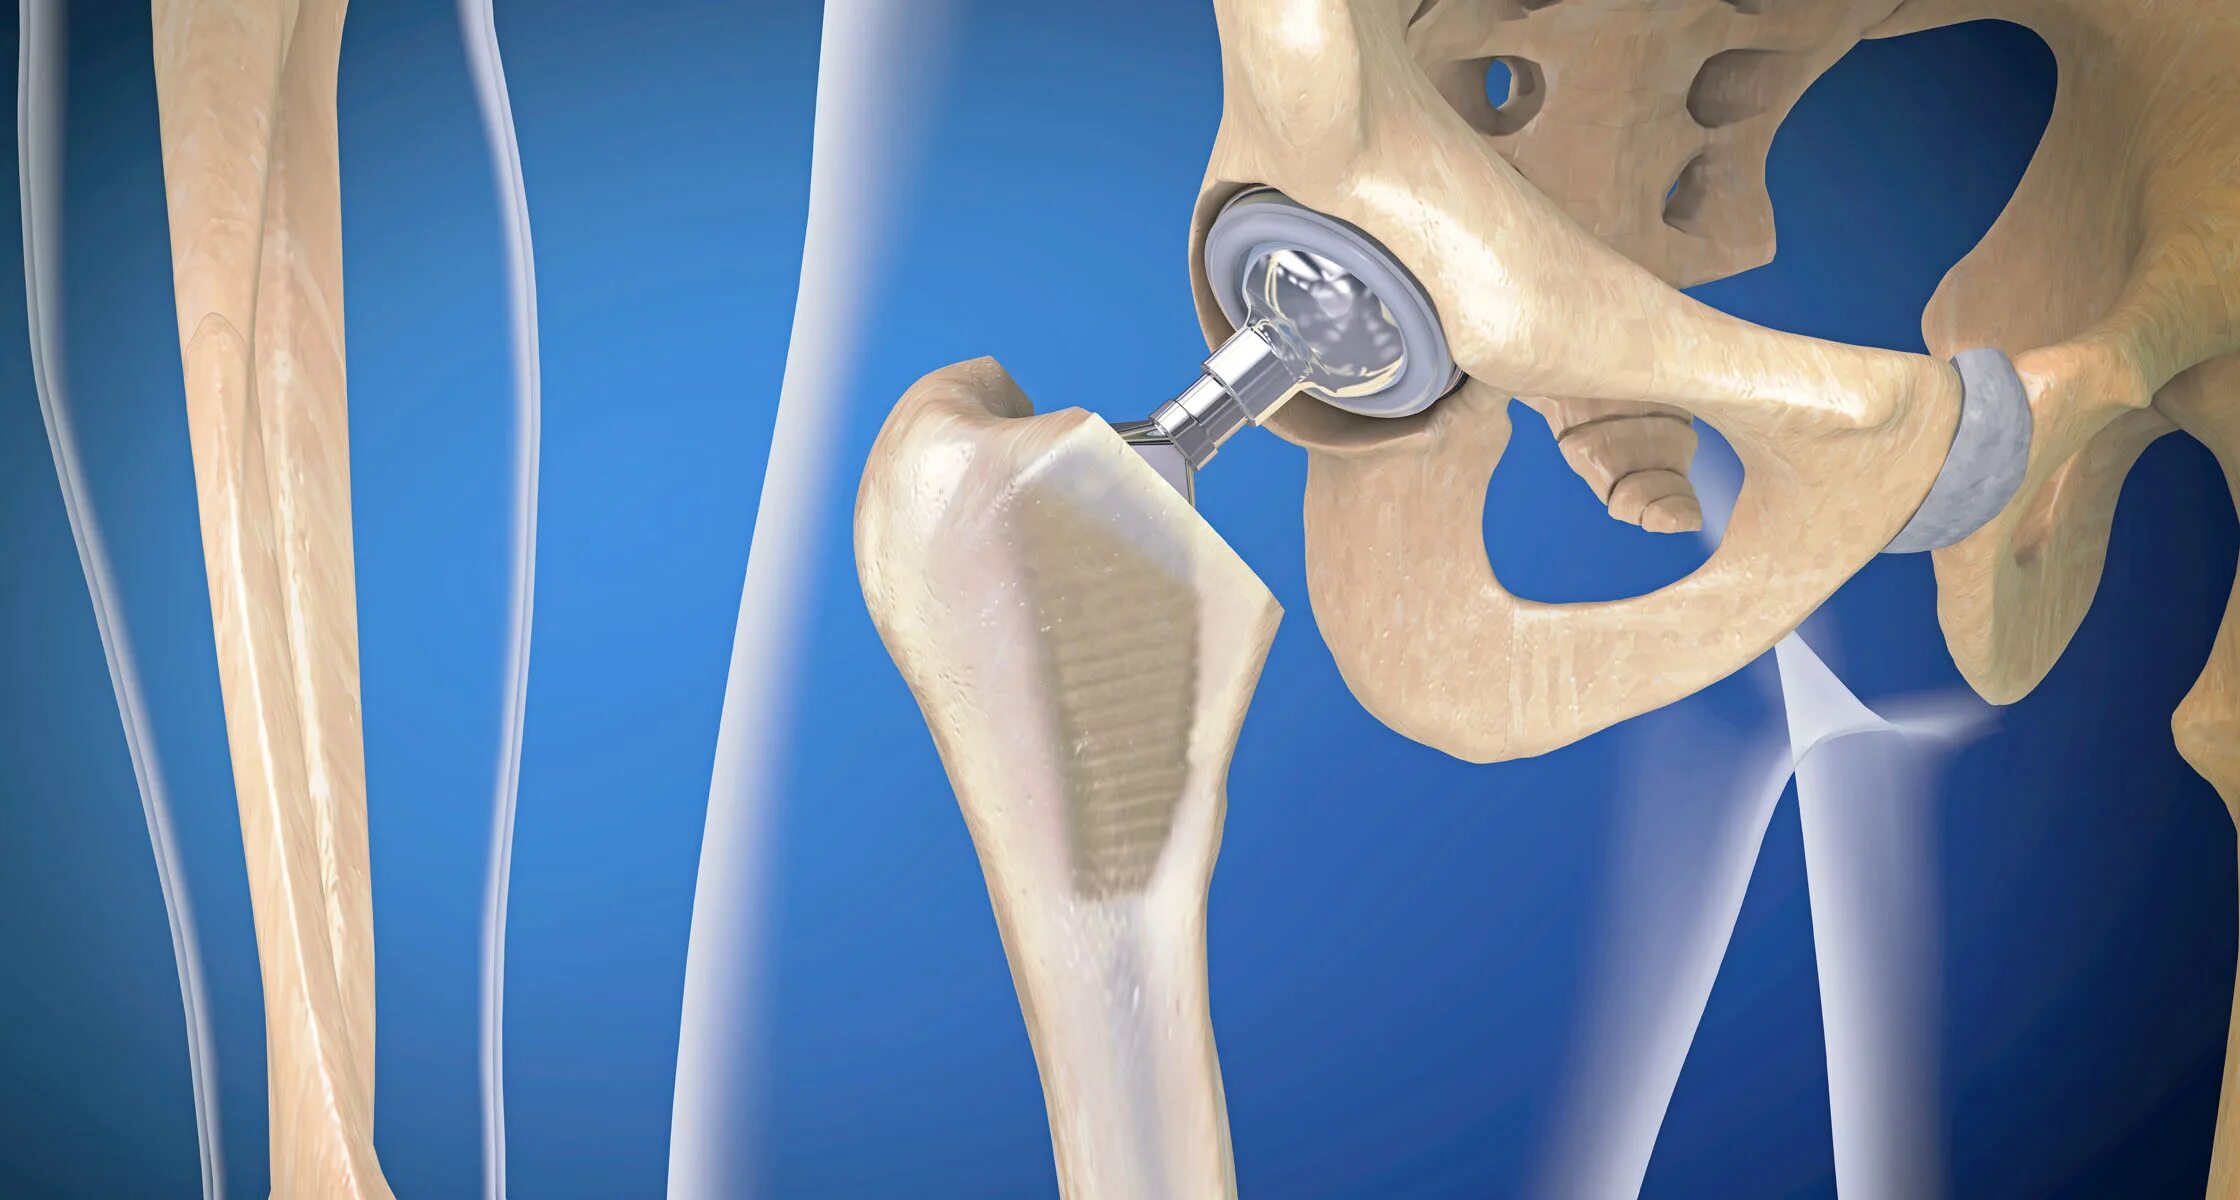

Протезирование суставов по квоте